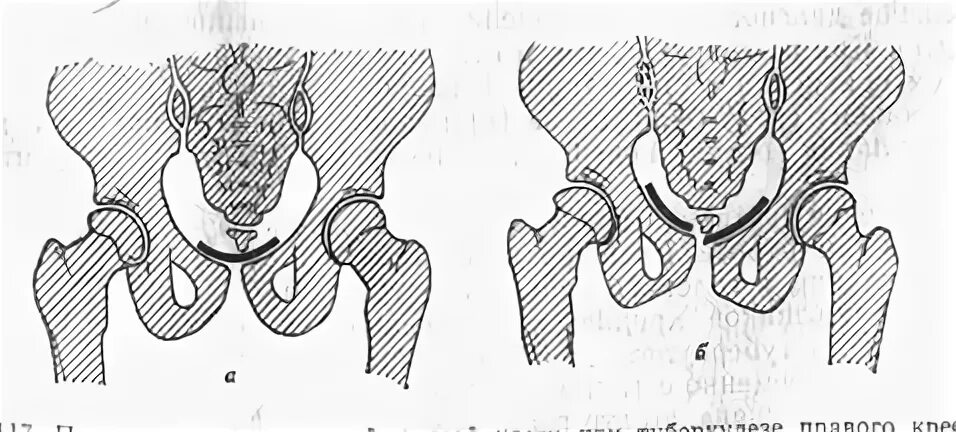

Разрыв крестцово подвздошного сочленения